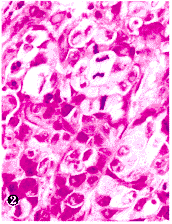

图2 CNE-2裸鼠移植瘤HE染色(×100)

Fig.2 H&E stained slide of CNE-2 nude mice transplant

Showing apoptotic bodies and mitotic neoplastic cells(×100)

CNE-1移植瘤分化较好,在HE染色下细胞分界较清楚,有时可见细胞间桥和个别角化细胞(插页1图1),而CNE-2移植瘤则分化较差,细胞分界不清楚,无细胞间桥和个别角化细胞(插页1图2)。CNE-1及CNE-2各代裸鼠移植瘤组织在HE染色下均可见到多灶性肿瘤细胞死亡。细胞死亡灶中有“皱缩性坏死”(“shrinkage necrosis”)和凝固性坏死两种形态,而常以“皱缩性坏死”为主(插页1图3)。“皱缩性坏死”的细胞相互分离,体积缩小,胞浆高度嗜酸性,内含1~2个固缩而深染的核,少数细胞甚至不含核(插页1图3)。在TUNEL染色下,这些“皱缩性坏死”的细胞呈强阳性的末端标记信号。凝固性坏死细胞轮廓尚存,胞浆染色较浅,核已消失(插页1图3)。在所谓非细胞死亡灶的HE染色下仍可见到少数位于细胞间和被瘤细胞吞噬的凋亡小体(插页1图2)。凋亡小体表现为不含或含染色质的微小嗜酸性小体,被吞噬在细胞内的凋亡小体旁常有一个空晕。在TUNEL染色下除了这些凋亡小体呈阳性信号外,许多HE染色下被忽视的凋亡小体都可被检测到(插页1图4)。每个高倍视野(10×40)至少有100个凋亡小体信号。